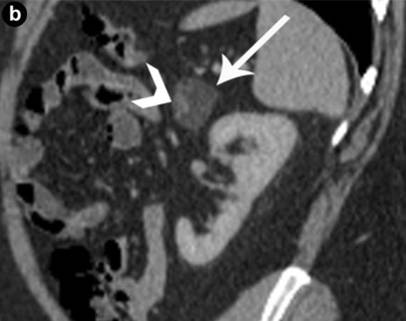

Various radiologic investigations were used in the pre-operative evaluation of the lesions. Imaging studies included CT scans, MRI and endoscopic ultrasound (EUS). All lesions were exophytic with one cyst originating from the head of the pancreas, two from the body, and three from the tail region. One patient had papillary projections into the lesion. Multiphase enhanced CT scan of the abdomen typically revealed a well-defined hypodense mass with imperceptible walls and Hounsfield units in the range of 15-20 (Figures 1 and 2). MRI of the abdomen was performed in one case and again showed a well-circumscribed exophytic lesion of the body of the pancreas with high T1 signal intensity, intermediate T2 signal intensity, with no enhancement following intravenous contrast administration (Figure 3). magnetic resonance cholangiopancreatography (MRCP) sequences did not show any continuity with the ductal system.

Figure 3. A 63-year-old male with incidentally discovered pancreatic mass (Case #5). a. Unenhanced axial CT shows a well defined mass arising off the superior aspect of the pancreatic body (arrow) measuring above fluid attenuation, and incompletely evaluated without intravenous contrast. Due to decreased glomerular filtration rate, MRI was used to characterize the lesion. Axial T2 weighted images (b.) show a well defined mass of intermediate signal intensity, which shows inherent high signal intensity on unenhanced T1 weighted images (c.). T1 post-contrast subtraction imaging (d.) shows the mass having a black non-enhancing center, with a thin rim of peripheral enhancement. |